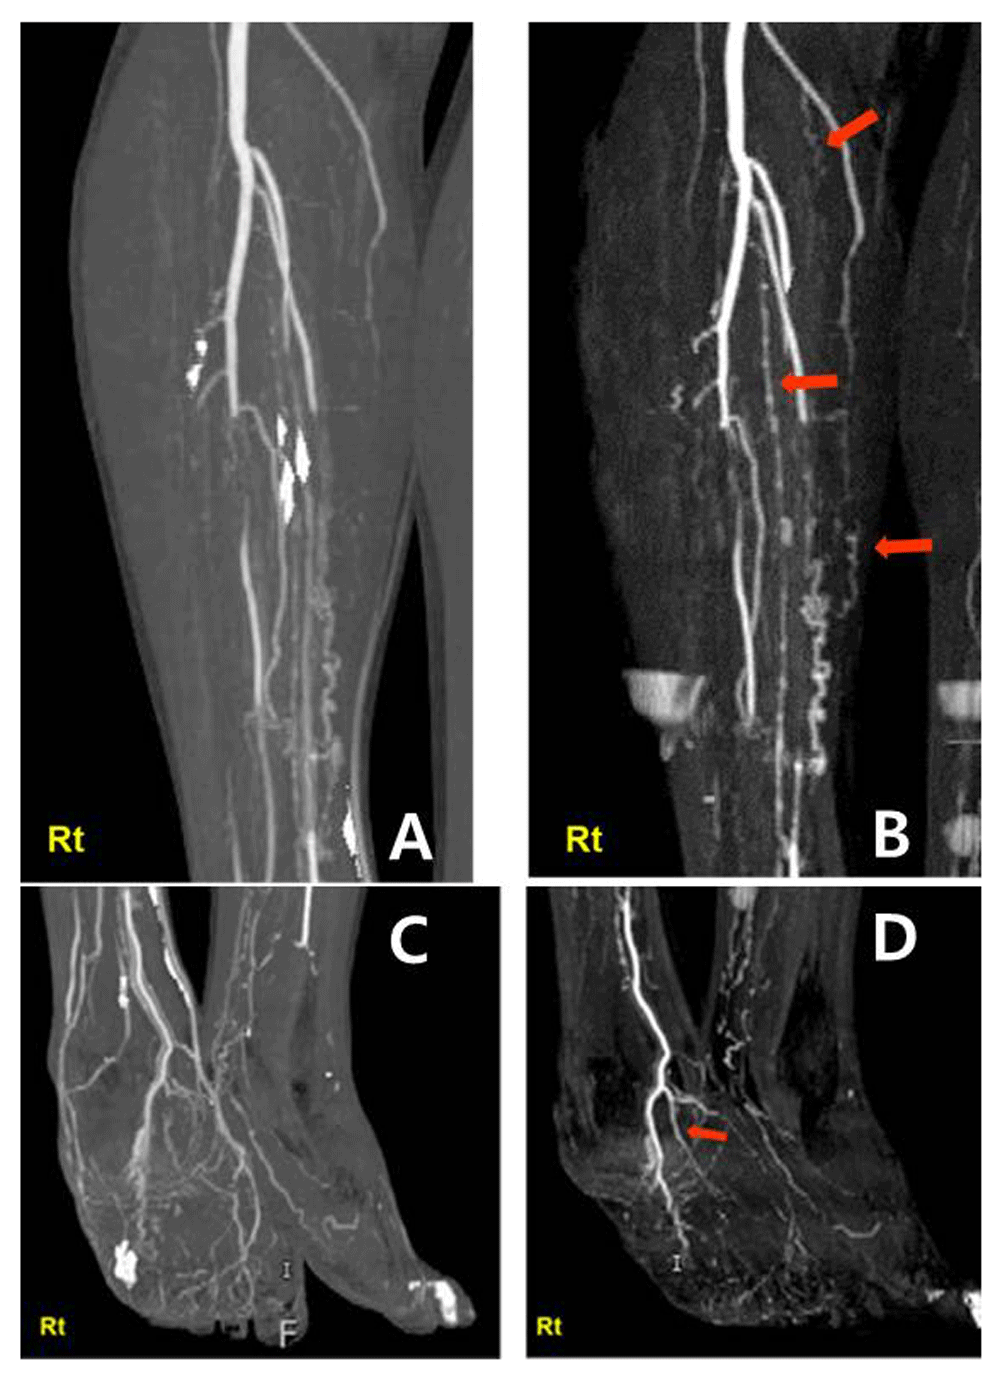

The clinical manifestation of the patient with diagnosis of Buerger's Buerger's Disease Ultrasound The combination of clinical assessment and the distinctive appearance of vessels affected by bueger's disease on colour. Buerger’s disease (thromboangiitis obliterans) is a rare disease that affects the blood vessels in your legs, arms, feet and hands. Thromboangiitis obliterans (tao), also called buerger disease, is a nonatherosclerotic, segmental, inflammatory. Clinical features and assessment by colour duplex ultrasound. Because of the. Buerger's Disease Ultrasound.